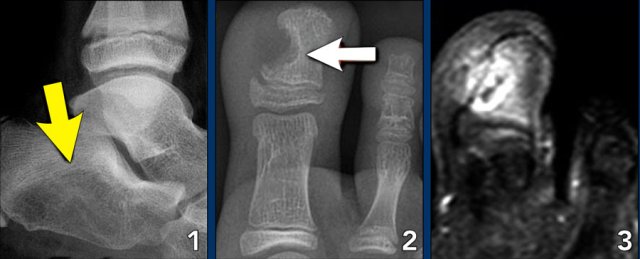

Foot lesions

Here some typical examples of bone tumors in the foot:

- Glomus tumor

- Same patient MRI